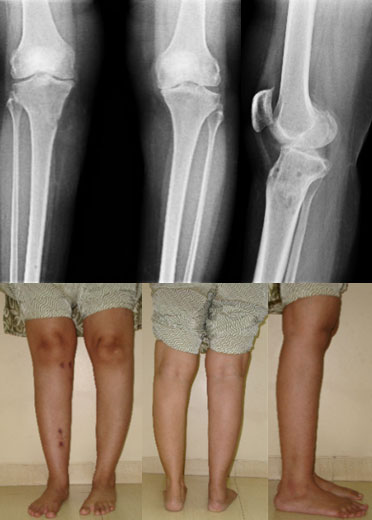

| The clinical pics and full length x-ray before surgery show a significant varus deformity in both the tibiae. The right side was operated first as the right side was more painful. The yellow line on the x-ray shows the load bearing axis, which is passing through the inner side of the knee. The red and the green lines show the varus angulation (bowing of the leg). |

| The x-rays and clinical pictures 4 weeks after fixator removal, showing excellent correction. The osteotomy has healed well. The patient is walking well without any trouble on the right side. The left side also has significant medial compartment osteoarthritis and joint space reduction alongwith varus deformity. |